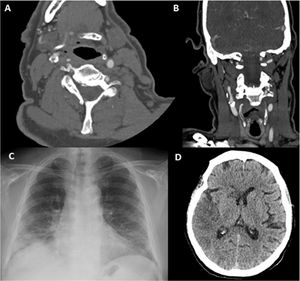

Paciente 6. A) Angio-TC axial, trombo endoluminal sobre placa de ateroma en la arteria carótida interna derecha (ACI).B) Reconstrucción coronal de angio-TC, placa de ateroma calcificada y trombo endoluminal sobre placa C) Radiografía de tórax,infiltración difusa bilateral por COVID-19. D) TC de cráneo sin contraste, con signos de infarto cerebral en el territorio de la ACMderecha.